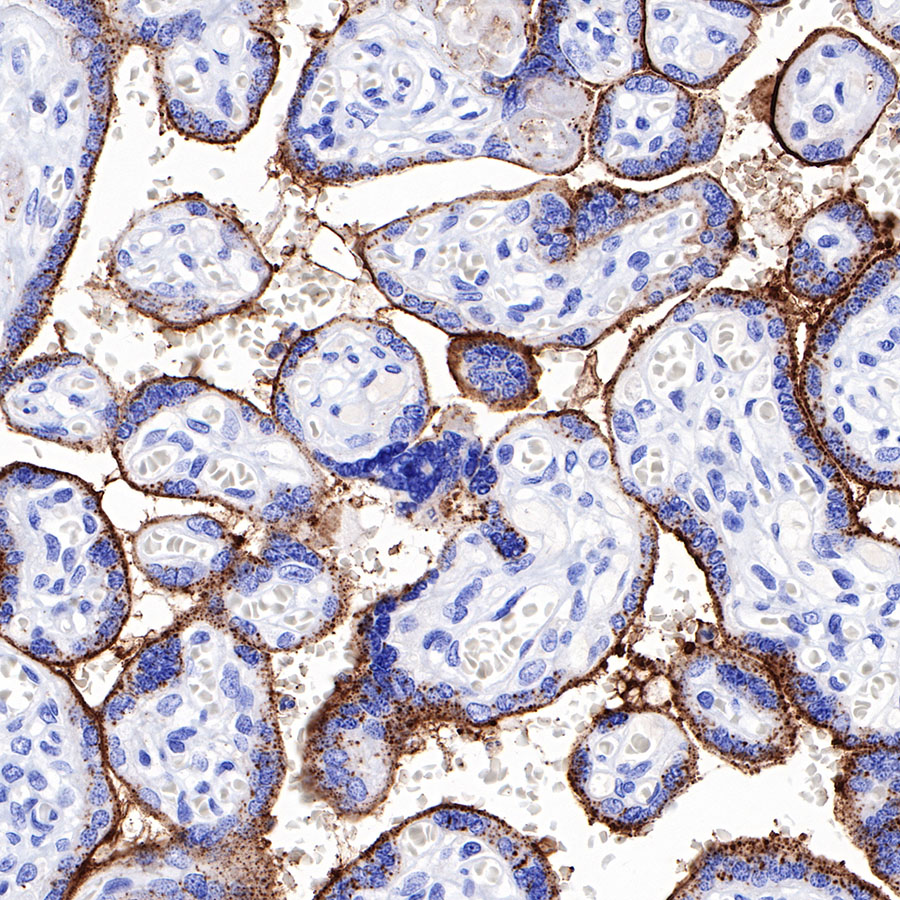

Syndecan-1 (CD138) is mostly restricted to epithelia, and bears heparan sulfate chains that are capable of interacting with a large array of polypeptides, including extracellular matrix components and potent mediators of proliferation, adhesion and migration. For this reason, it has been studied extensively with respect to carcinomas and tumor progression. Frequently, but not always, syndecan-1 levels decrease as tumor grade, stage and invasiveness and dedifferentiation increase. However, in some tumors, levels of syndecan-1 increase, but the characterization of its distribution is relevant. There can be loss of membrane staining, but acquisition of cytoplasmic and/or nuclear staining that is abnormal. Moreover, the appearance of syndecan-1 in the tumor stroma, either associated with its cellular component or the collagenous matrix, is nearly always a sign of poor prognosis [PMID: 33921767].

Immunohistochemistry